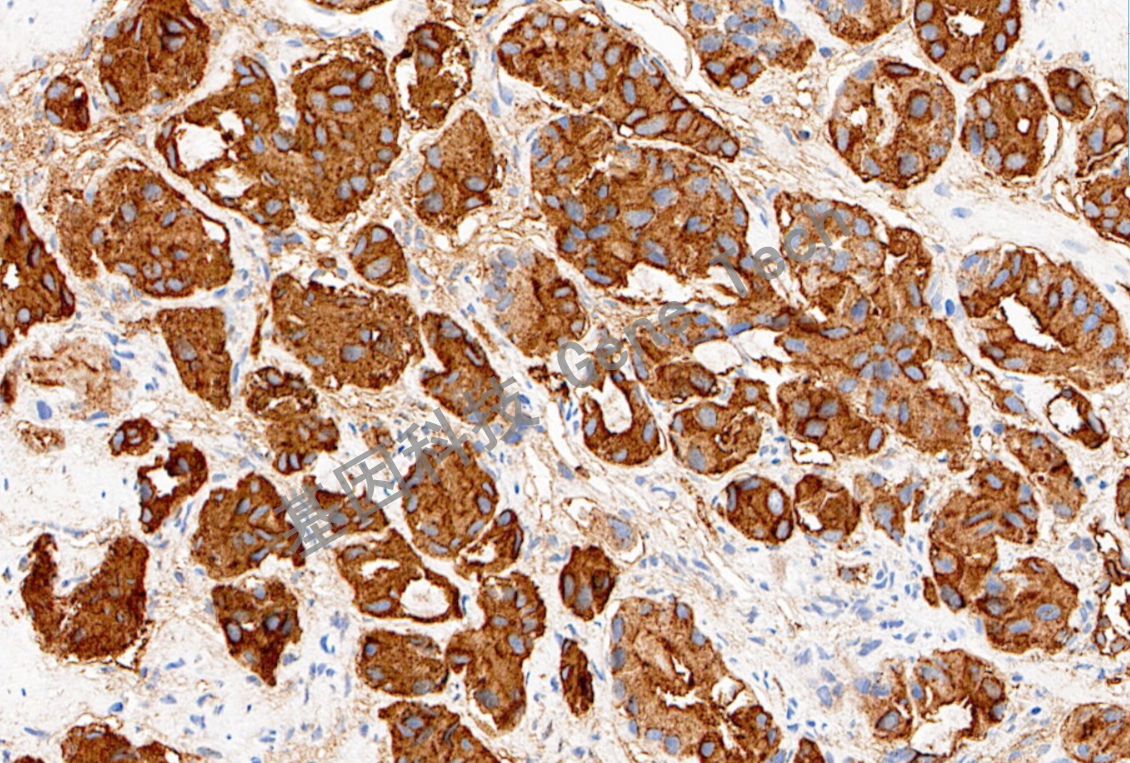

MUC-1 鼠抗人 MUC-1 抗體試劑(免疫組織化學(xué))

| 克隆號:GR503 | 種屬:鼠 | 適用染色系統(tǒng):GTvisionTM |

| 預(yù)處理:高pH熱修復(fù) | 陽性部位:細胞膜/細胞漿 | 陽性對照:乳腺癌/膀胱癌 |

| 簡介:粘蛋白 1(MUC-1) 又稱多形性上皮粘蛋白(polymorphi cepithelialmucin,PEM),屬粘蛋白家族成員。MUC-1 是一種重要的腫瘤標(biāo)志物,其在腫瘤細胞的表達模式與正常細胞不同,主要體現(xiàn)在以下二個方面:(1)MUC-1 在腫瘤細胞表面的表達量較正常細胞顯著升高;(2)MUC-1 在正常細胞上呈極性分布,集中位于腺上皮細胞的腺腔面;而在腫瘤細胞上MUC-1 卻呈失極性,均勻地分布于細胞的表面。該抗體主要用于乳腺癌的診斷與研究。 | ||

| 乳腺癌石蠟切片,用 MUC1(GT2083)染色,細胞膜/細胞漿陽性,DAB 顯色。 | ||